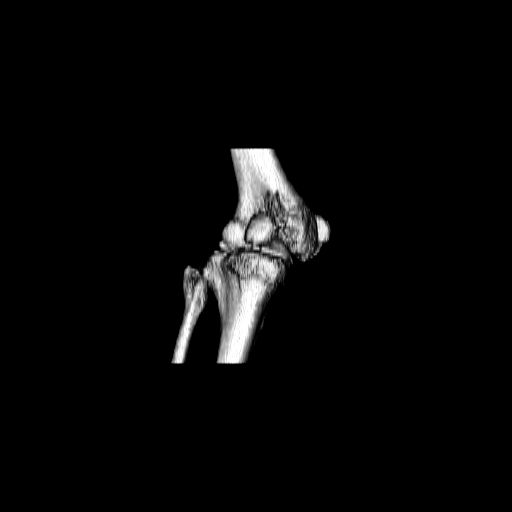

При внутрисуcтавных переломах трехмерные (3D) изображения, кроме красивого снимка, не дают полную информацию о состоянии отломков, самыми информативными являются корональные срезы на КТ и обычная длинная ренгенограмма конечности для сравнения оси конечности.

Фронтальные внутрисуставные переломы мыщельков бедра, так называемые Hoffa fracture, не частые, но встречающиеся переломы, в основном они связаны с травмой высокой энергией.